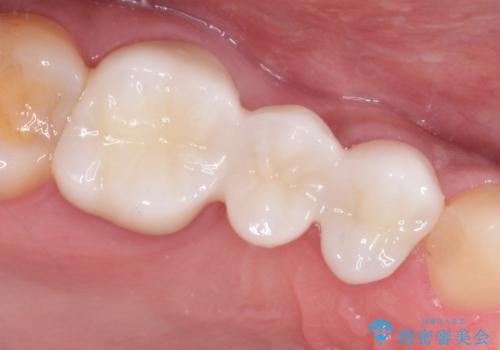

以前は保険治療で作られた金属のブリッジを装着されていましたが、オールセラミックブリッジを装着することにより、審美的にも改善されました。